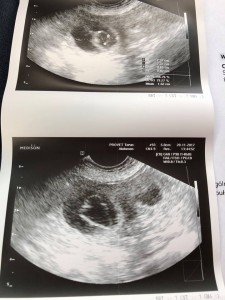

Dziś w Naszej hodowli urodziło się 6 suczek.

Wyjątkowy prezent.

Mama i małe czują się dobrze.